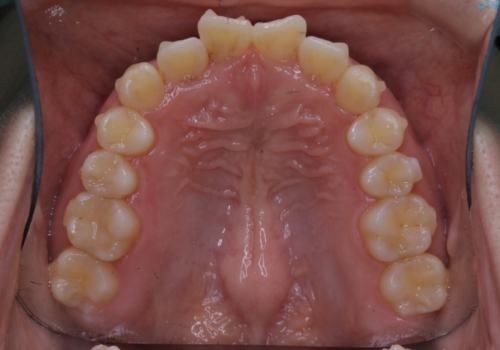

- 前歯が捻転していることを主訴に来院された方です。元々は部分矯正をご希望されていましたが、噛み合わせ等総合的に治療していくためインビザラインにて全顎的に治療を行うこととしました。

元々は上の前歯部の捻転のみの治療をご希望されていましたが、下の前歯もがたつきがあることや噛み合わせがかなり深いことを説明しました。後戻りのリスクを抑えるために全顎的な治療をご提案しました。

捻転していた上顎前歯部の仕上がりにこだわり、何度か修正を行ったため、満足のいく仕上がりになったと大変喜んでいただけました。